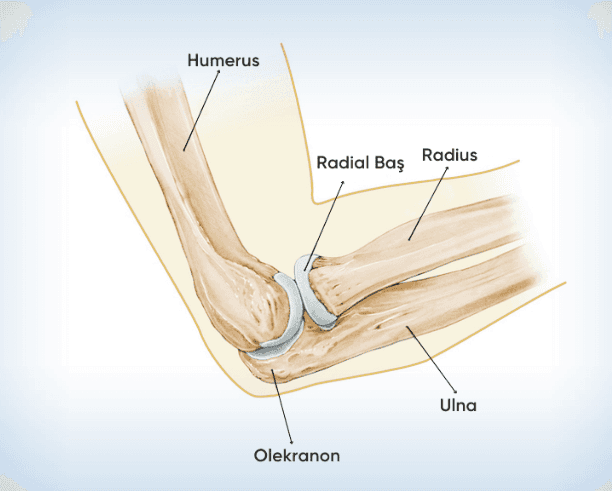

Dirsek Kırığı

Dirsek kırığı, dirsek eklemi vücudun en karmaşık eklerinden biridir. Dirsek kırıkları ise, el üzerine şiddetli şekilde...